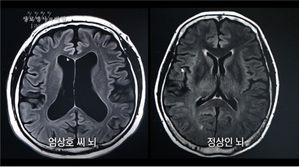

'생로병사의 비밀' 알코올중독·의존증, 심방세동·간경화·알코올성치매등 유발 영향과 치료법

[메가경제 유지훈 기자] 우리나라는 관대한 음주문화로 인해 음주율, 사회적 과음자율, 알코올중독자율 모두 높은 나라에 속한다. 이렇다 보니 우리나라 국민정신건강 실태조사에서도 알코올 의존증은 정신과적 질환 중 단연 높은 유병률을 보인 ...